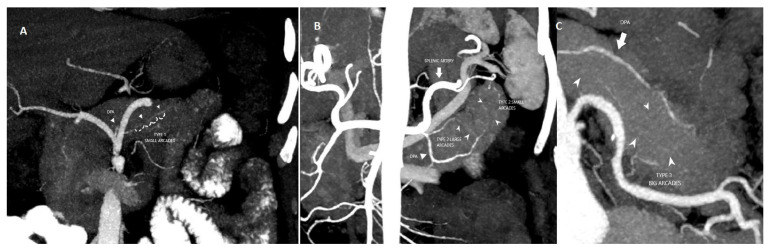

Background/objectives: The aim was to investigate the association between variations in the dorsal pancreatic artery (DPA) and intrapancreatic arcade anatomy with Whipple procedure outcomes and postoperative complications.

Results: After excluding cases that did not meet the study criteria, a total of 284 patients were included in the study. DPA was visualized in 55.98% (159/284) of patients, while the intrapancreatic arcade was observed in 25% (71/284). The most common origin of the DPA was the splenic artery in 69.2% (n = 110) of patients, followed by the superior mesenteric artery in 17.6% (n = 28). The frequency of intrapancreatic arcade anatomy variations was as follows: type 1: 28.2% (n = 20), type 2: 49.3% (n = 35) and type 3: 22.5% (n = 16). Arcade type 4 anatomy was not detected. Postoperative pancreatic fistula (POPF) complication was found to be statistically significantly higher in patients with type 3 anatomy (p = 0.042). The 90-day mortality and long-term mortality rates did not differ among the groups based on the variations in both DPA and intrapancreatic arcade anatomy types.

Conclusions: Patients with intrapancreatic arcade type 3 anatomy had a higher risk of POPF complications. Determination of preoperative arcade type by computed tomography (CT) angiography may help to predict the risk of POPF.